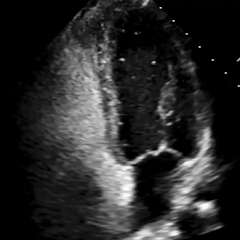

经胸右心声学造影:经左肘静脉注入震荡生理盐水(8mL生理盐水+1mL回抽静脉血+1mL空气经震荡制成),上腔、右房依次显影,造影剂完全充盈右心后,平静呼吸时,左房内即可探及微泡回声,约20-30个/切面/帧;瓦氏呼吸释放即刻,左房内探及微泡回声,不可计数。

术前静息状态经胸右心声学造影(中量)